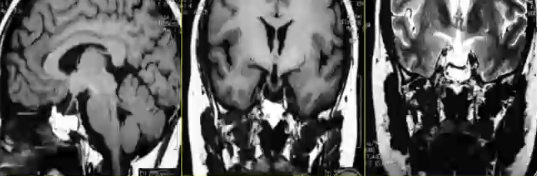

图例:女,37岁,视力下降2月,MRI发现垂体区囊性占位,手术为垂体囊肿。术后视交叉下移。

√垂体单纯囊肿为垂体少见病变,以垂体及邻近结构压迫产生症状

√CT、MRI表现:

1)垂体窝内的液体密度或信号

2)有囊壁结构,液体局限化

3)占位效应可与空蝶鞍鉴别